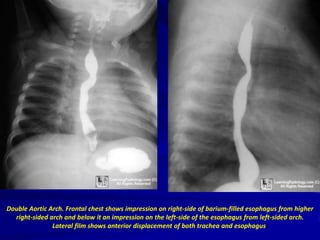

DOUBLE AORTIC ARCH

CHILD WITH RECURRENT PNEUMONIA

Double Aortic Arch. Frontal chest shows impression on right-side of barium-filled esophagus from higher

right-sided arch and below it an impression on the left-side of the esophagus from left-sided arch.

Lateral film shows anterior displacement of both trachea and esophagus.